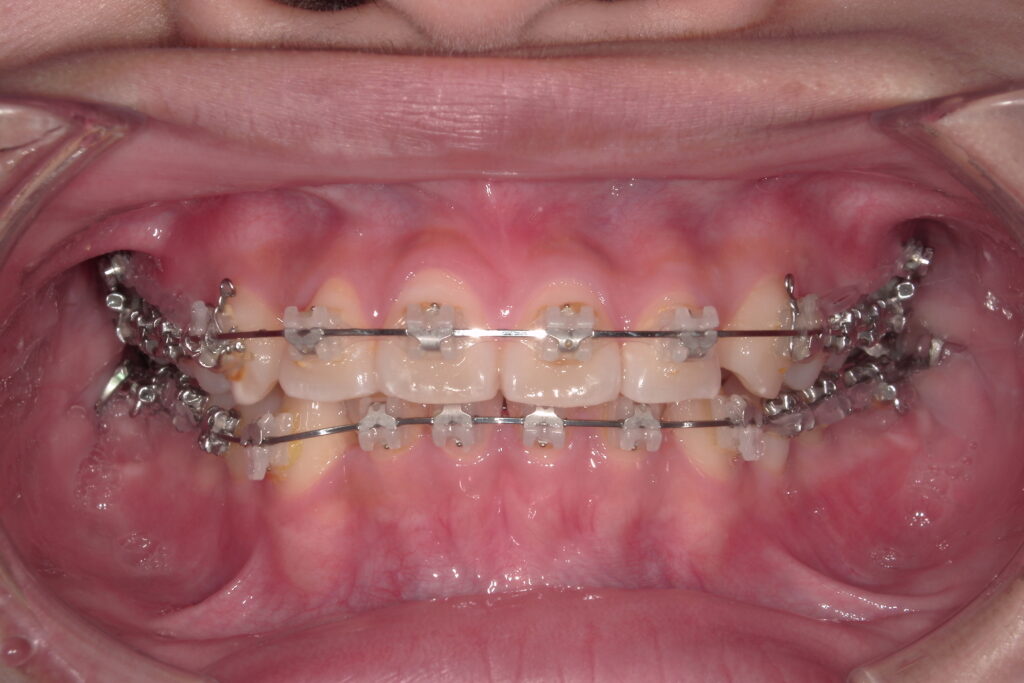

表側矯正は、歯の表面にブラケットと呼ばれる小さな装置を装着し、それにワイヤーを通して歯を少しずつ動かしていく治療方法です。もっとも古くから使われているスタンダードな方法で、幅広い症例に対応できるのが大きな魅力です。最近では、アンカースクリュー(ネジ)を併用することで、従来の治療よりも出っ歯や過蓋咬合(深い咬み合わせ)の治療が効率的に進められるようになりました。当院では、歯の色になじみやすいオールセラミックブラケットや、白くコーティングされたホワイトワイヤーも選択可能で、目立ちにくさにも配慮しています。

- 幅広い不正咬合に対応可能(出っ歯・受け口・開咬・叢生など)

- 比較的費用が抑えられる

- 装置の安定性が高く、効率的に動かせる

- 金属アレルギーでも使用できる(クリアティウルトラのみ)

装置が見えるため、審美的にはやや劣る

歯磨きがしづらく、虫歯のリスクがやや高まる

装着直後は痛みや違和感を感じることがある